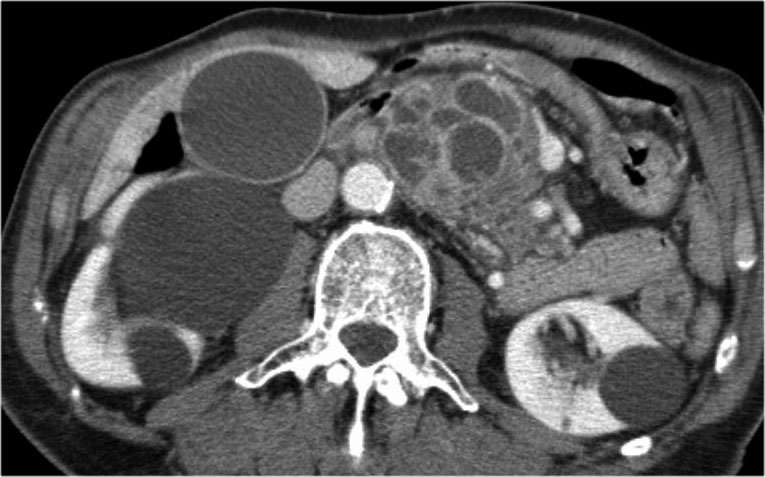

Một ví dụ khác về u nang tuyến thanh dịch (Hình).

Hình ảnh sau tiêm thuốc cản quang bên phải cho thấy tổn thương giảm tỷ trọng với vôi hóa trung tâm ở thân tụy và ngấm thuốc nhẹ của các vách ngăn.

Lưu ý rằng trên CT rất khó nhận ra bản chất dạng nang của các tổn thương này và có thể nhầm lẫn với ung thư biểu mô tuyến tụy.

MRI sẽ dễ dàng thể hiện bản chất dạng nang của các tổn thương này (hình).

Chuỗi xung T2W với xóa mỡ (fatsat) thể hiện rõ tổn thương tăng tín hiệu dạng thùy múi với sẹo trung tâm, đây là hình ảnh đặc trưng của SCN.